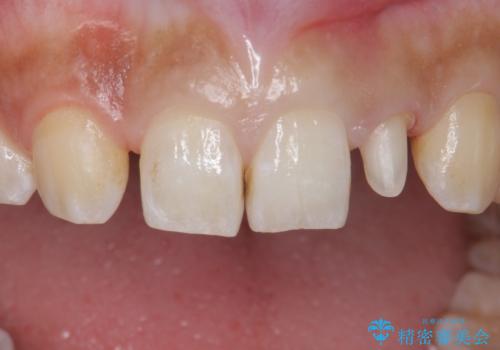

変色した前歯をキレイにしたい ジルコニアクラウンでの修復

- 左上の前歯の変色が気になるとのことで来院されました。

もともと小さい歯(矮小歯)に樹脂が盛り足されている状態でした。

今後の変色をなくすために樹脂ではなくセラミックでの治療を行います。

- 左上2:仮歯+ジルコニアクラウン/11,000円+110,000円費用は治療当時の料金となります

セラミックでの治療をすることにより今後の変色を抑えることができます。

色・形ともに改善することができ大変喜んでいただけました。